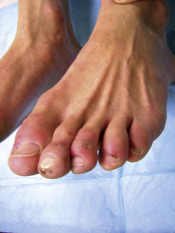

Cutaneous: livedo reticularis ( Fig. 3.27 ) , cutaneous necrosis, skin ulcerations ( Fig. 3.28 ), gangrene of digits

FIG. 3.27

Bluish, netlike, reticular pattern of discoloration involving the lower extremities associated with circulating antiphospholipid antibodies in this patient.

FIG. 3.28

Lacelike appearance of the skin with blue mottling in this patient with an ulcer due to infarction.

(Fitzsimons Army Medical Center Collection)